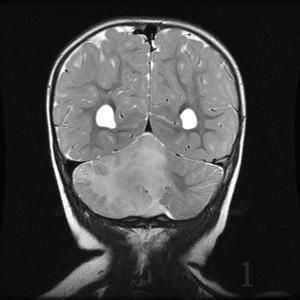

腦瘤,包括各種顱內(nèi)腫瘤,有良性和惡性之分。惡性腦腫瘤又稱“腦癌”。因為顱腔之輪廓全是骨骼,所以如果腦生瘤腫,則會使顱腔內(nèi)之壓力增加,因而產(chǎn)生頭痛,嘔吐,視線不清,抽筋,昏迷等。那么腦瘤到底能不能治好呢?

按照衛(wèi)生組織的分級,腦腫瘤一共分為四級,從一級到四級,惡性程度也逐漸增高。其中一級腫瘤為良性腫瘤,能夠通過手術順利切除,患者能夠獲得痊愈。而二級腫瘤就是惡性度比較低的腫瘤了,在全部切除后應用放療,化療輔助治療,也能達到治愈程度,但三級以上的腫瘤的治療效果就明顯降低了,在手術后需要輔助放療和化療,且在這些治療后仍有可能復發(fā),也就是說絕大部分惡性腦腫瘤難以治好,需要定期復查。